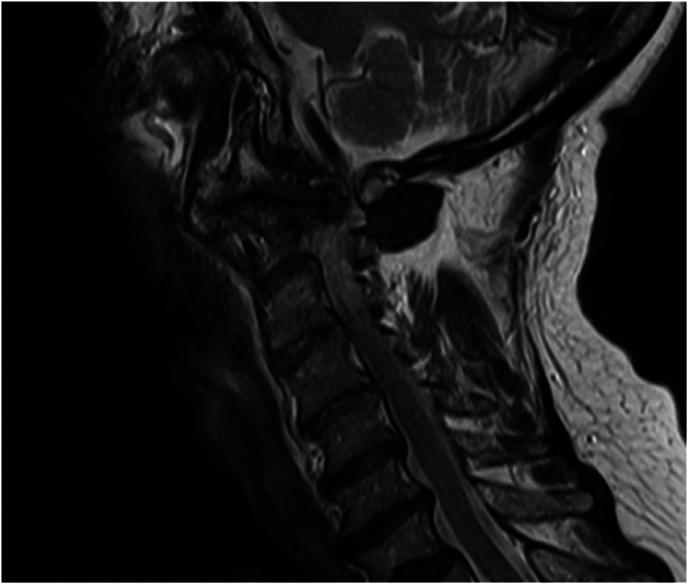

Patients with RA in which follow-up cervical MRI studies (at least 3 years apart) were available were identified retrospectively in two tertiary care centers. Patients without definitive deformity at baseline were included in the algorithm. Patients were assessed for RA-associated cervical spine deformity, defined as presence of pannus and/or degeneration of the facet joints of C0-C1 and/or C1-C2 on follow up MRI.

A deep learning model was developed to predict the development of pannus and/or facet joint deformity at the craniocervical junction of patients with RA. Future research should focus on large-scale validation of this model with diverse sites and identifying the role of the subaxial spine in the risk of deformity at the level of the craniocervical junction during the course of disease.